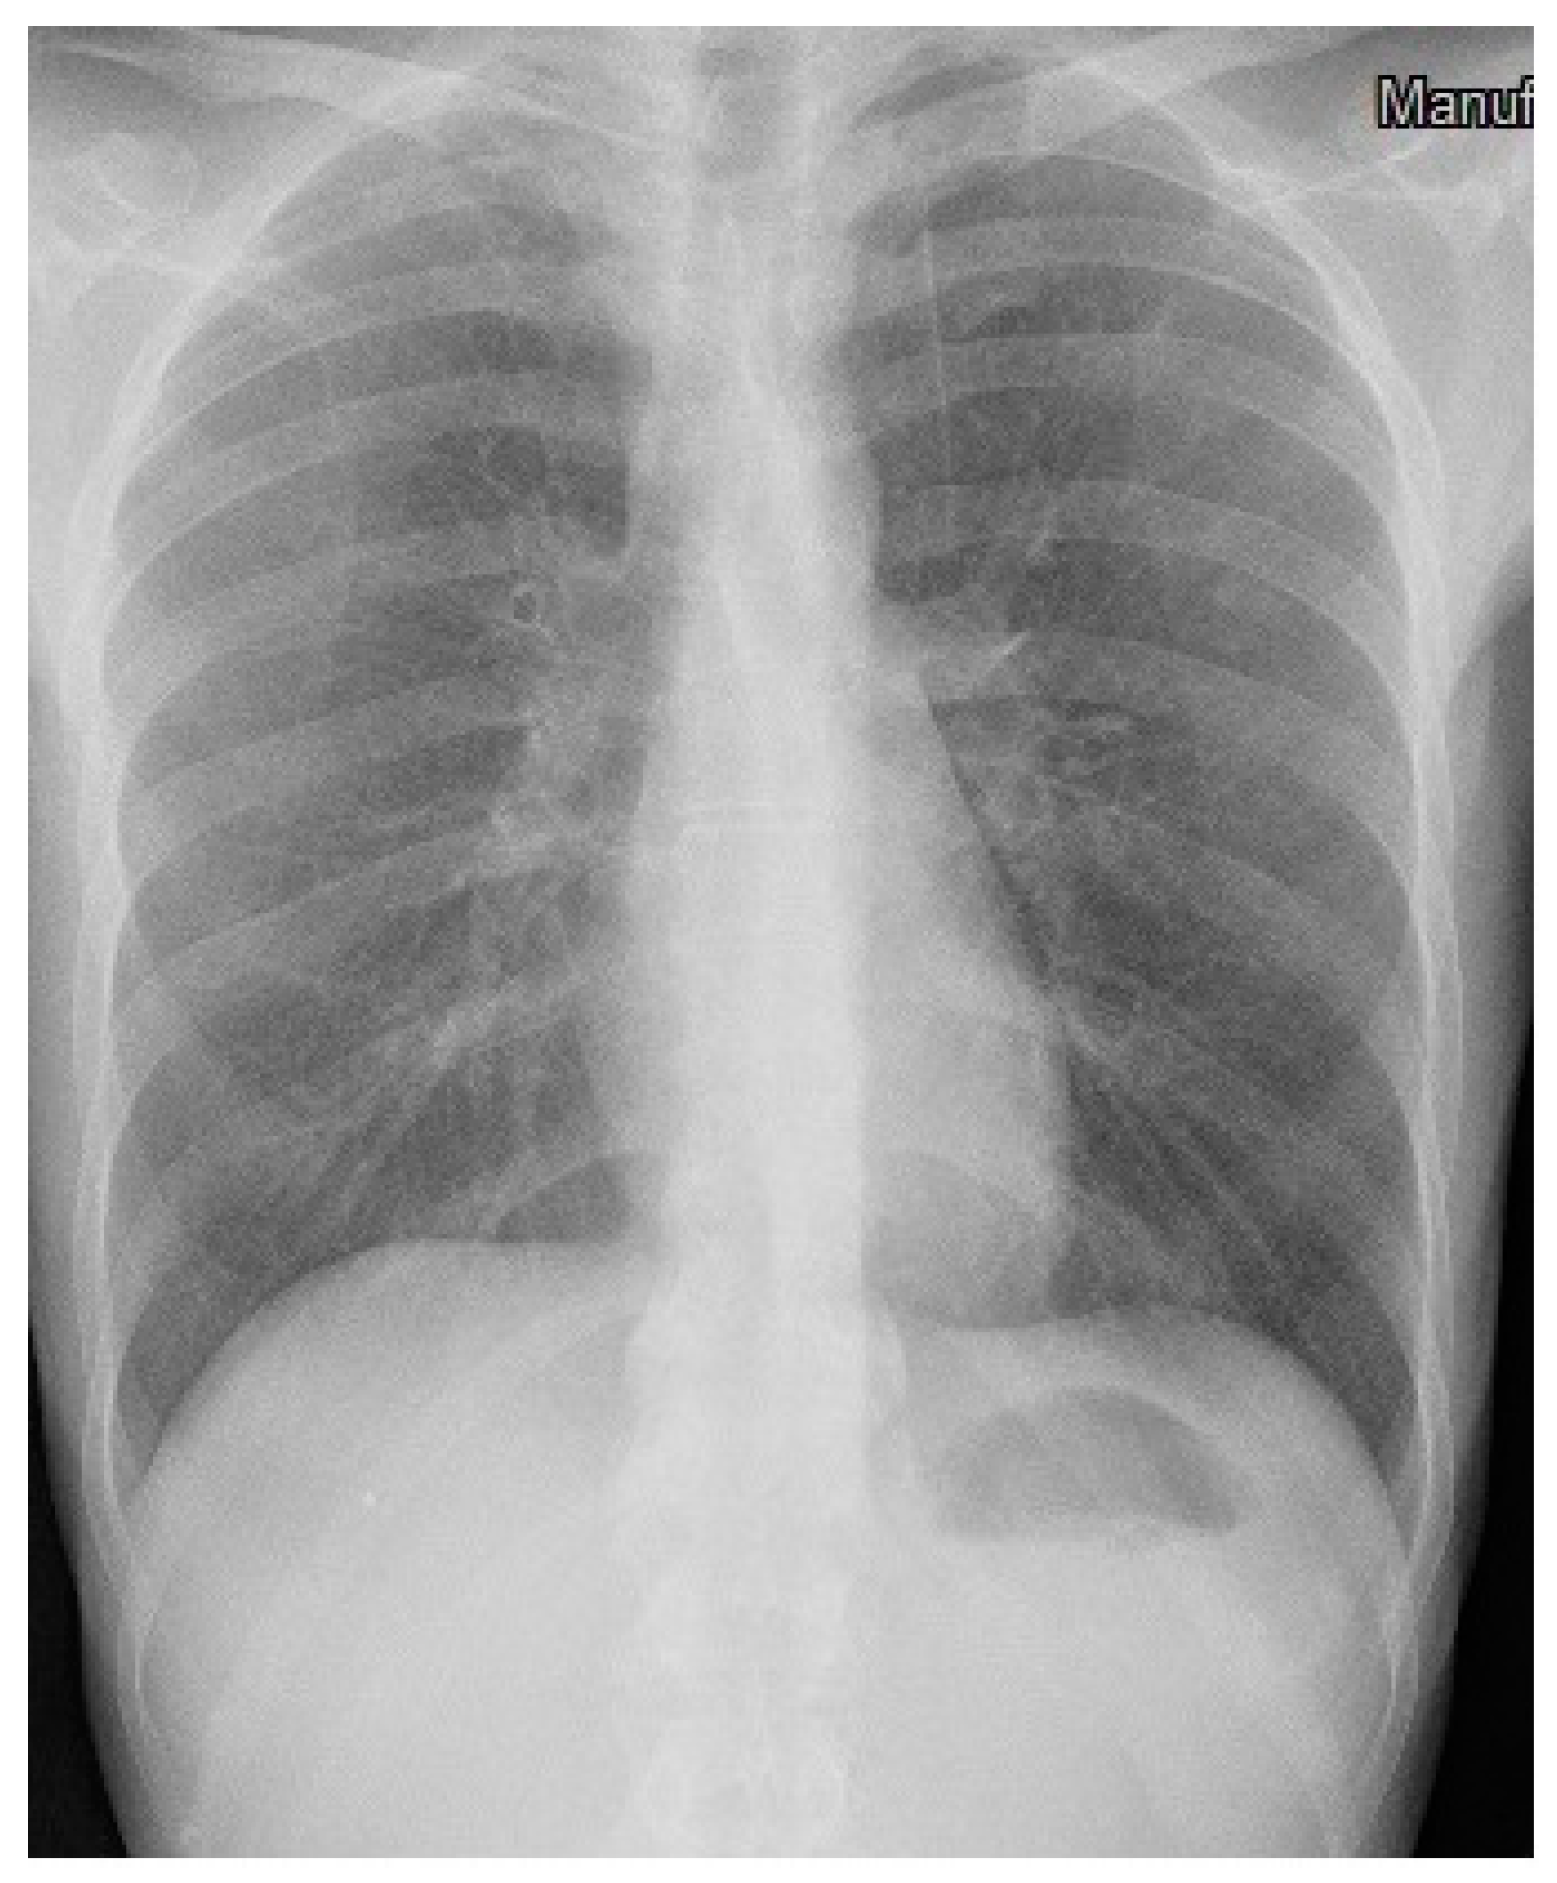

3. Case Description

4. Clinical Case Management